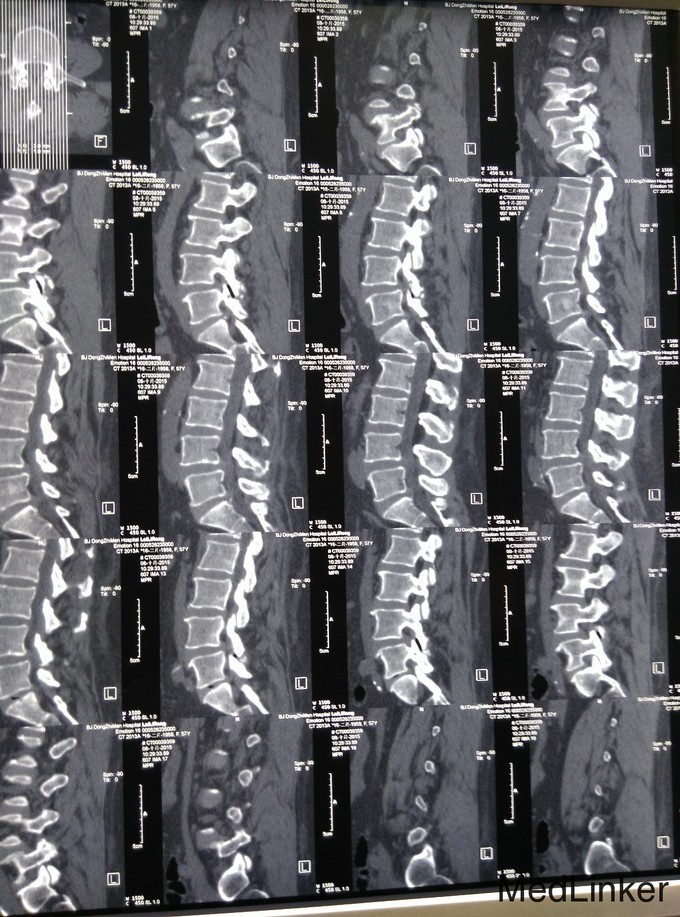

查体:脊柱生理弯曲存在,无腰椎侧突畸形,腰4-骶1椎旁压痛和深部扣击痛(+),腰部活动稍受限,直腿抬高试验双侧阴性,双下肢浅感觉无明显减退,双下肢肌力4级,双下肢膝反射和踝反射稍减弱,髌阵挛、踝阵挛未引出。病理反射未引出,肛周浅感觉正常,肛门反射正常。 腰椎CT及腰椎MRI示:L4-5、L5-S1椎间盘突出,椎管狭窄,黄韧带肥厚,相应硬膜囊受压。

诊断:腰椎管狭窄症、腰椎间盘突出、腰椎骨关节病 治疗:入院后完善相关检查,无明显手术禁忌症,于手术室全麻下行腰4-5、腰5-骶1椎板切除、椎管减压、椎弓根内固定术,